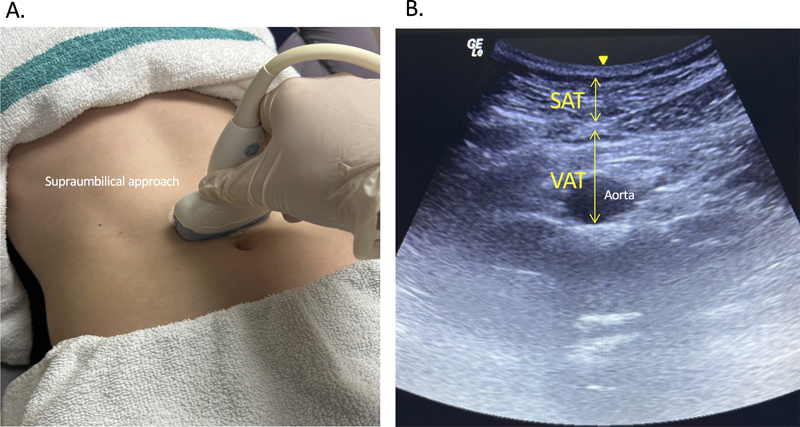

In 1990, Armellini et al. reported the first use of ultrasonography to measure VAT (more specifically intraperitoneal adipose tissue) thickness in 50 female subjects.40 In their technique, a 3.5-MHz transducer was applied just superior to the umbilicus in subjects lying in the supine position. Images were recorded using the B-mode. To estimate VAT thickness, the authors measured the distance between the posterior surface of the rectus sheath and the posterior wall of the abdominal aorta (Figure 4). Their ultrasonographic measurements correlated significantly with VAT measurements calculated from CT scans taken at the level of the fourth lumbar vertebra (r = 0.67, p < .001). Further studies established the repeatability and accuracy of this technique in various patient populations.41–43

Figure 4

Figure 4. Supraumbilical approach to measure SAT and VAT. (A) Curvilinear probe applied 1 cm superior to umbilicus. (B) Labeled B-mode image.